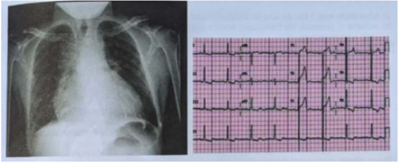

Homem de 58 anos apresentou dor súbita e intensa em face anterior do tórax irradiada para o pescoço com início há 2 horas e com pouca melhora 1 hora após uso de analgésico oral. Foi submetido a cineangiocoronariografia para estratificação de doença arterial coronariana aterosclerótica no dia anterior. Refere ser tabagista e hipertenso de longa data e nega outras comorbidades. A radiografia de tórax e o eletrocardiograma feitos na sala de emergência do hospital são demonstrados nas figura abaixo. A pressão arterial é de 160 x 110 mmHg, e a frequência cardíaca de 98 bpm. Qual a conduta mais adequada?